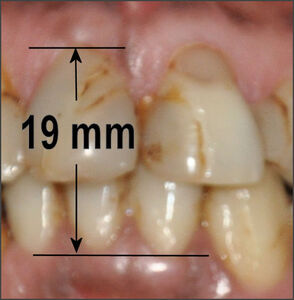

The Median Shimbashi Measurement (MSM) is between 17-18 mm from the cementoenamel junction (CEJ) of the upper central incisors to the cementoenamel junction of the lower central incisors with the teeth in centric occlusion.29 See Figure 7. Some have confused the first set of measurements by Dr. Hank Shimbashi, which in a Class I control group averaged 19 mm at rest position, with the same distance later averaged between 17 mm and 18 mm in centric occlusion. While these are not absolute values, they are useful guidelines to re-establishing a comfortable vertical dimension and it has been widely reported that patients with worn dentitions and severe malocclusions often measure well below 17 mm.30